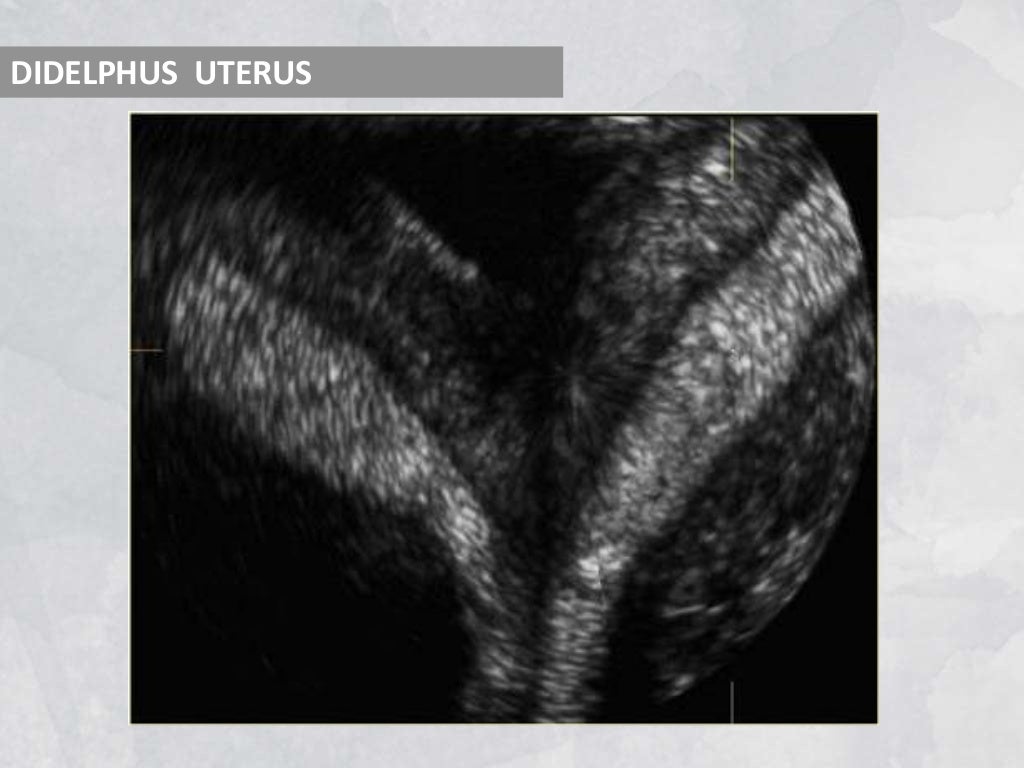

From www.slideshare.net

Imaging in obstetrics & gynaecology (part 1 Gynaecological scans in Imaging Techniques In Gynaecology the hysterosalpingogram (hsg) had been considered the gold standard for imaging the uterine corpus for benign disorders. Several technical advances in recent decades currently allow superb imaging of female. the role of imaging in the management of a wide range of gynaecological disorders is well established. although ultrasound is the primary imaging modality for most gynecologic diagnoses. Imaging Techniques In Gynaecology.